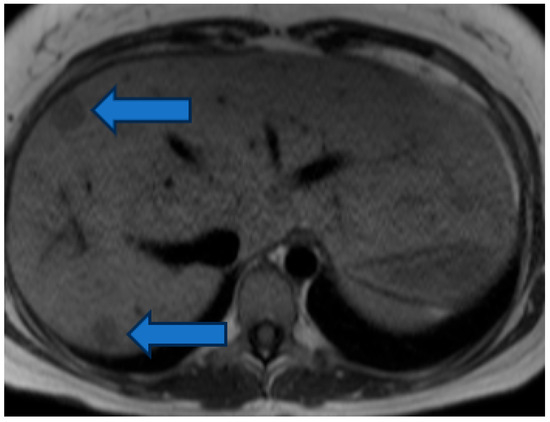

Incidental Hepatic Findings in Cardiac Magnetic Resonance Imaging Examinations in Patients with Congenital Heart Disease: A Pilot Study

Objectives: During cardiac magnetic resonance imaging (cMRI) exams in patients with congenital heart disease (CHD), incidental liver abnormalities are increasingly found. However, no systematic data exist on the incidence of liver lesions in patients with different CHDs. In order to gain a first overview, we retrospectively analyzed cMRI examinations from the last 10 years at our institution. Methods: CMRI examinations including T2-weighted images covering parts of the liver were performed on 899 patients with CHD at our institution between 2014 and 2024. The cMRI examinations were analyzed by a medical student, a pediatrician, a radiologist, and a pediatric cardiologist. Liver lesions were defined as atypical liver parenchyma, showing T2 hyper- or hypointensity compared to the surrounding liver tissue. Results: Liver lesions were found in 9.5% (85/899) of all cMRI studies; of these, 89% ((76/85) of cases) were unknown at time of cMRI, 96% (82/85) were T2 hyperintense, and 38% (32/85) were larger than 1 cm. The patients with liver lesions were older (29 years vs. 22 years, p < 0.0001). There were no sex differences in the incidence of liver lesions or differences in right or left ventricular function (LVEF: 57% vs. 58%, p = 0.78; RVEF: 55% vs. 54%, p = 0.35). The patients with univentricular hearts, transposition of great arteries after atrial switch operation, and atrial septal defects showed the highest incidence (18%, 17%, and 21%, respectively). However, 9% of patients with left heart-sided valve disease also showed liver lesions. Conclusions: Incidental findings of liver lesions in cMRI examinations of patients with CHD are reasonably high with almost 10%. In the growing population of adults with CHD, liver monitoring might be helpful to assure overall patient health. Full article

Figure 1